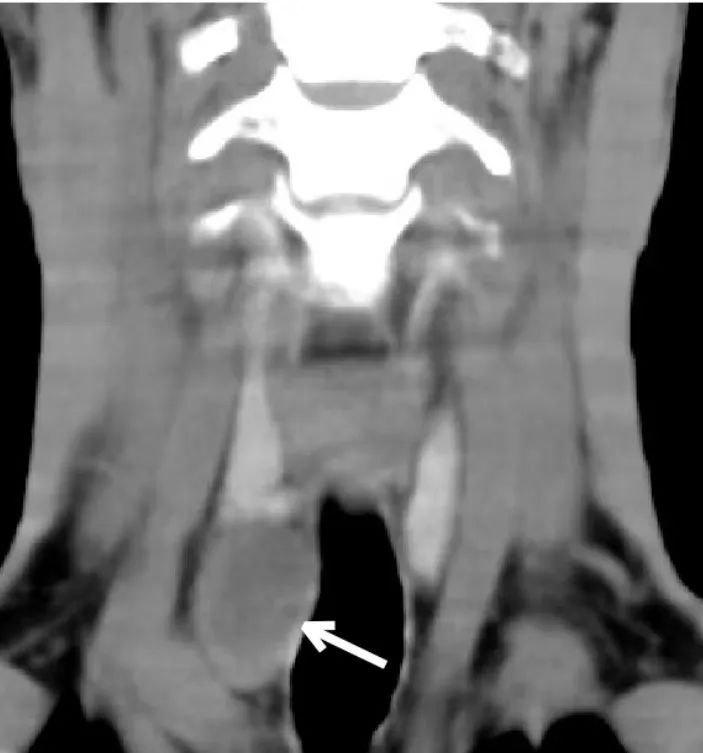

为了进一步寻找疾病的元凶,我院内分泌代谢科专家赵家胜主任医师亲自打电话给患者,建议他到同济医院来进一步检查。普通外科甲状腺中心吴社华主任接诊了患者并将其收住入院,甲状旁腺同位素检查显示右下甲状旁腺明显增大,放射性核素摄取功能明显增强(图7),证实了甲旁亢的诊断。颈部CT冠状面重建显示右侧甲状腺下方低密度软组织肿块(图8),完整切除该肿块(图9),病理证实为甲状旁腺腺瘤,患者的血钙从术前的3.23mmol/L降至术后的2.26mmol/L,甲状旁腺激素从术前的1830pg/ml降至10.6pg/ml。至此,隐藏在患者体内真正的元凶终于被绳之以法。为了弥补骨钙的“历史欠账”,术后长期补充维生素D和钙片,以防治“骨饥饿综合征”的发生,目前患者仍在随访当中。

图8.右下甲状旁腺腺瘤(白箭头)